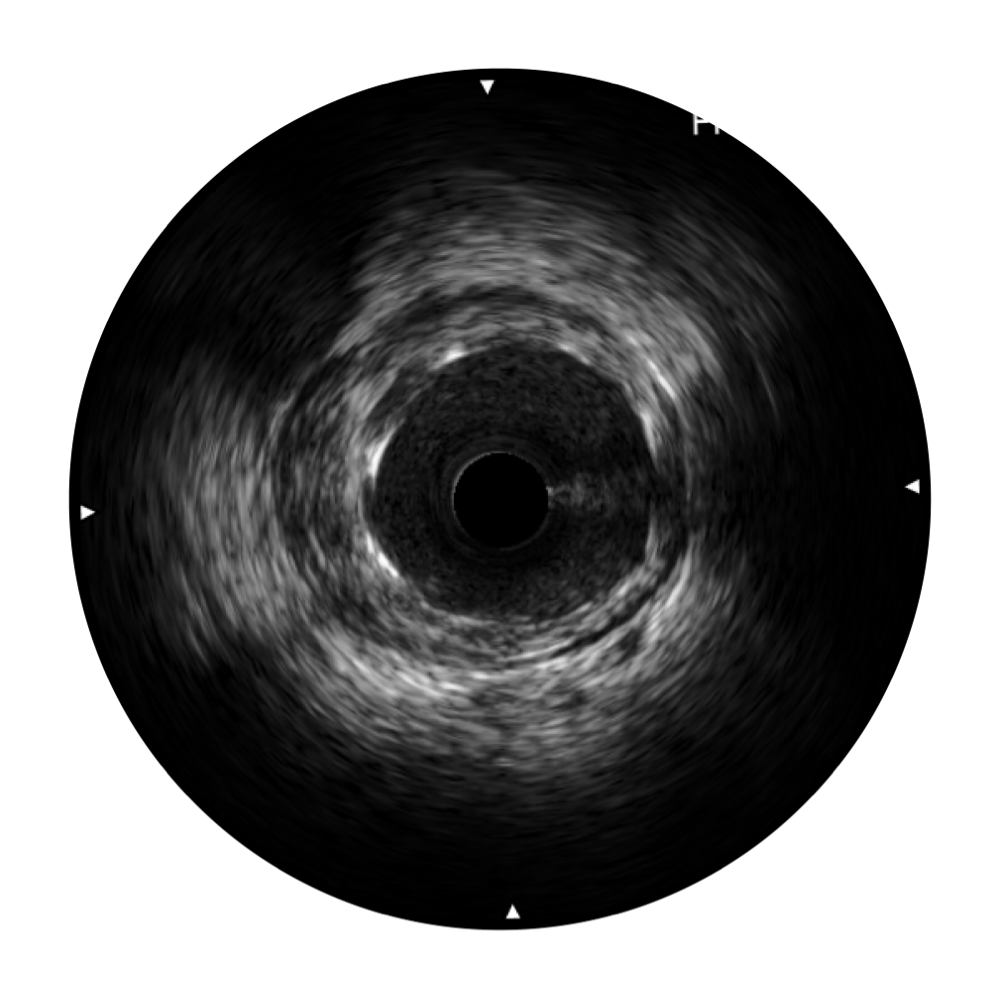

米兰官方网站宽频IVUS图像

对比传统IVUS导管成像,米兰官方网站宽频IVUS图像的近场支架梁显影更细腻,远场中膜外血管仍清晰可辨,兼顾远中近,兼顾分辨力与穿透深度